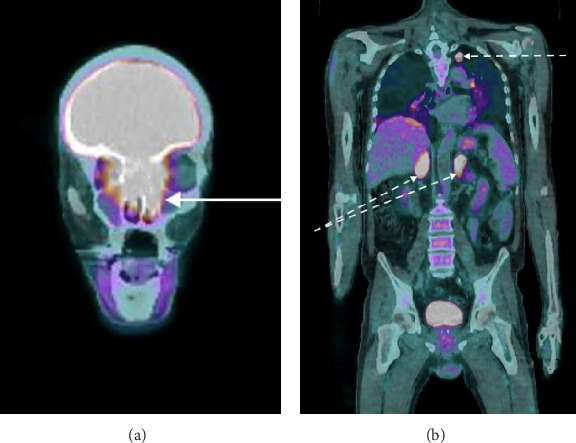

Background: Olfactory neuroblastoma (ONB) is a rare tumor of the nasal cavity. It may sometimes present with Cushing's syndrome due to adrenocorticotropic hormone (ACTH) secretion, making it challenging to diagnose. Methods: A 65-year-old man with hypokalemia and general weakness presented to the emergency department for Cushing's syndrome. Brain imaging revealed a tumor originating from the ethmoid bone with peritumoral cysts. The first biopsy suggested an ectopic corticotropic pituitary adenoma or a well-differentiated neuroendocrine tumor. However, the second biopsy confirmed an ONB, as suspected by the otolaryngologist. Treatment consisted of neoadjuvant chemotherapy, surgery, and radiotherapy. Results: The patient was cured of Cushing's syndrome and remained in remission at 10 years of follow-up. Conclusion: An unusual mode of discovering ONB is via the diagnosis of Cushing's syndrome caused by ACTH secretion, which may manifest throughout the course of follow-up. Imaging analysis and discussion with pathologists are essential to achieve an accurate diagnosis.